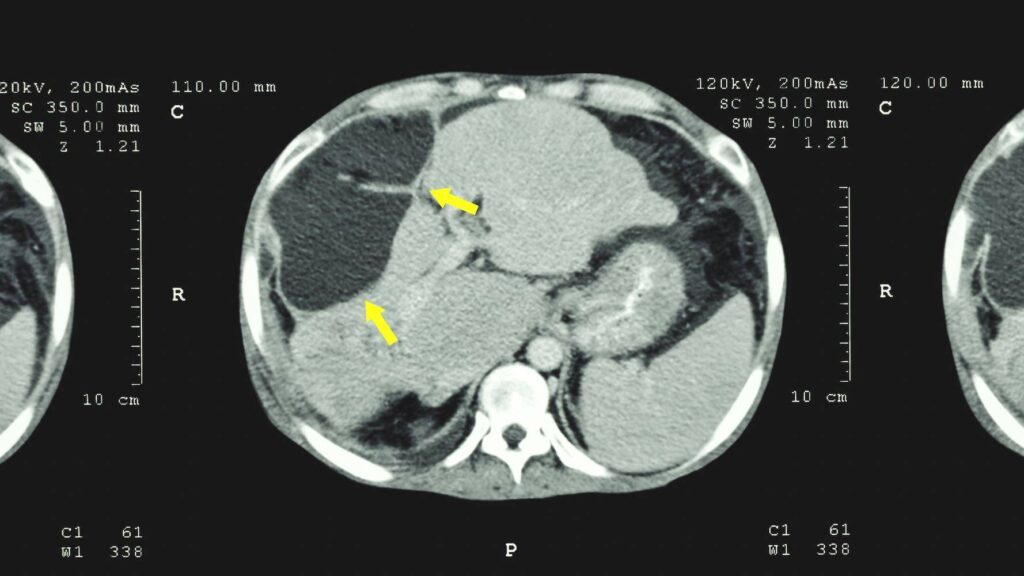

Gutartige (nicht krebsartige) Tumore sind weniger gefährlich als bösartige Tumore. Sie verursachen oft keine Symptome und werden daher erst durch eine CT-, Ultraschall- oder MRT-Untersuchung diagnostiziert. Die häufigsten Arten von gutartigen Lebertumoren sind:

Die Größe des Tumors ist ein wichtiger Aspekt bei seiner Behandlung. Ein Tumor von 10 Zentimetern oder mehr wird als großer Lebertumor eingestuft. Hämangiome können eine Größe von 1 cm bis 10 oder sogar 20 cm (Riesenhämangiome) haben.